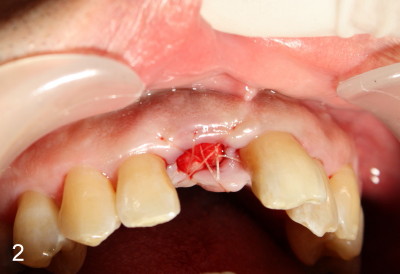

Two months after socket debridement, the wound appears to have healed with mild to moderate buccal plate atrophy (Fig.5).  Bone height is ~ 21 mm (Fig.6).  D2 short or long implant is planned.  Is this appropriate?

Two more weeks later, D2 implant (4.5x5.5x20 mm) is placed (Fig.9,10).  Fig.7 D2 thin socket former at ~ 16 mm depth, Fig.8 D2 medium socket former at ~ 19 mm.